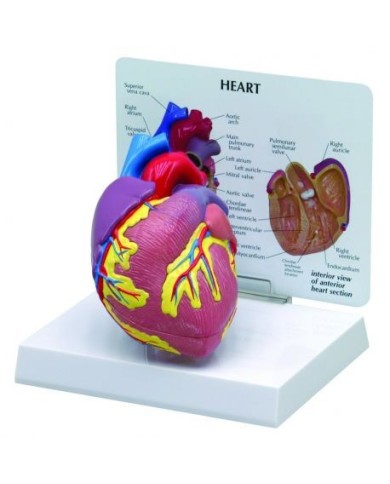

Con scheda descrittiva dettagliata

Modello di cuore di alta qualità scomponibile in 5 parti

Modello di cuore di alta qualità scomponibile in 5 parti